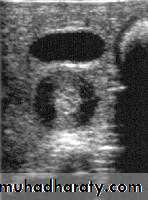

Hypertrophic pyloric stenosis refers to idiopathic thickening of gastric pyloric musculature which then results in progressive gastric outlet obstruction

In a normal situation, the pyloric muscle thickness (diame­ter of a single muscular wall on a transverse image) should normally be less than 3 mm (most accurate 3) and the length (longitudinal measurement) should not exceed 15 mm.